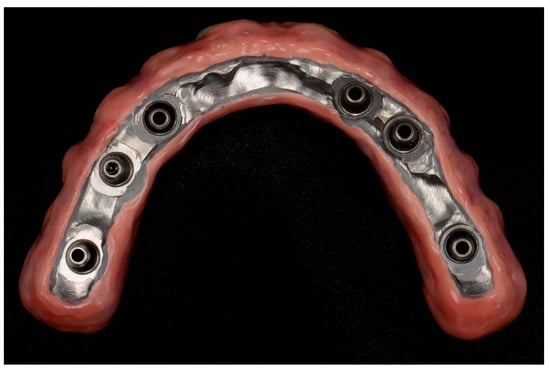

2.5. Prosthetic Protocol